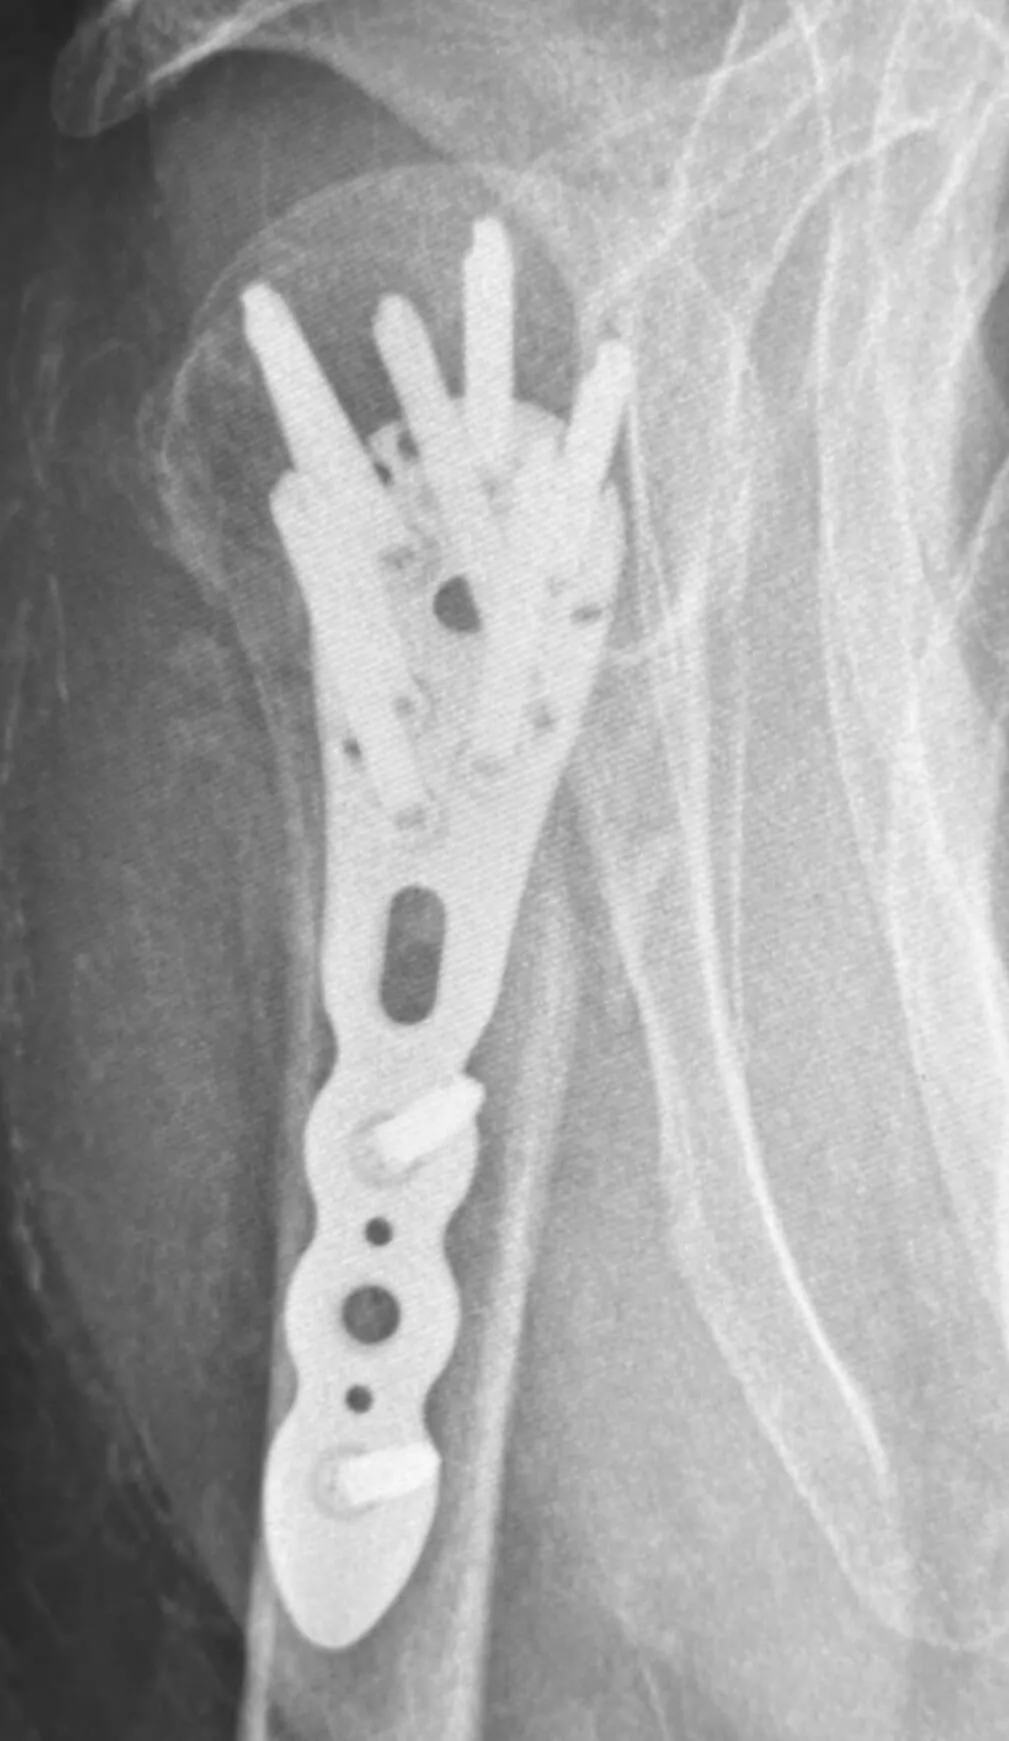

Operacja

Bezpośrednio po operacji

Złamanie bliższego końca kości ramiennej

Pacjentka, lat 76, doznała złamania w wyniku upadku z wysokości własnej. Złamanie miało charakter wieloodłamowy ze znacznym przemieszczeniem kątowym odłamów. Bez leczenia operacyjnego chora nie odzyskałaby dobrego zakresu ruchomości i siły mięśniowej.

Wykonano operację polegającą na otwartym nastawieniu złamania z prawidłowym ustawieniem odłamów kostnych oraz zespoleniem za pomocą płyty ze stabilnością kątową śrub. Dodatkowo przeprowadzono rekonstrukcję uszkodzonego aparatu więzadłowego barku i włączono pooperacyjną rehabilitację.

Pacjentka po 4 miesiącach odzyskała prawidłowy zakres ruchomości, siłę mięśniową oraz pełną funkcję kończyny.